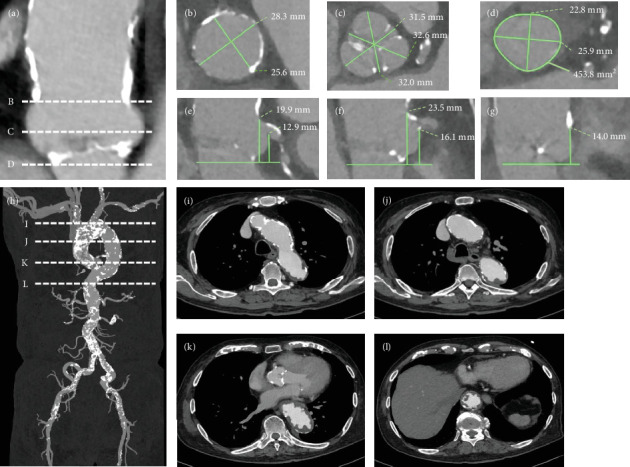

Patients on hemodialysis with concomitant severe aortic stenosis (AS) and multivessel coronary artery disease (CAD) are at high risk for surgical aortic valve replacement (SAVR) and coronary artery bypass grafting (CABG). Transsubclavian-transcatheter aortic valve implantation (TSc-TAVI) is a well-established alternative approach to transfemoral TAVI for patients with unfavorable femoral access. Herein, we report a case in which minimally invasive surgical treatment and TSc-TAVI were performed simultaneously in a patient with severe AS and multivessel CAD undergoing hemodialysis. An 85-year-old man undergoing hemodialysis for end-stage renal disease owing to severe AS (mean pressure gradient, 46 mmHg; aortic valve area, 0.75 cm2; and left ventricular ejection fraction, 59%) presented to our hospital with chest pain on exertion. Preoperative coronary angiography revealed significant stenosis of the left anterior descending (LAD) coronary artery and right coronary artery (RCA), requiring revascularization. However, the patient was not a good candidate for transfemoral TAVI because of a porcelain ascending aorta and a shaggy descending aorta observed on computed tomography. He was scheduled for concomitant right TSc-TAVI and minimally invasive cardiac surgery (MICS)-CABG after percutaneous coronary intervention (PCI) for the RCA. The treatment was successful. Simultaneous TSc-TAVI and MICS-CABG with PCI may be applied as a minimally invasive surgical treatment modality for patients with AS and CAD undergoing hemodialysis.